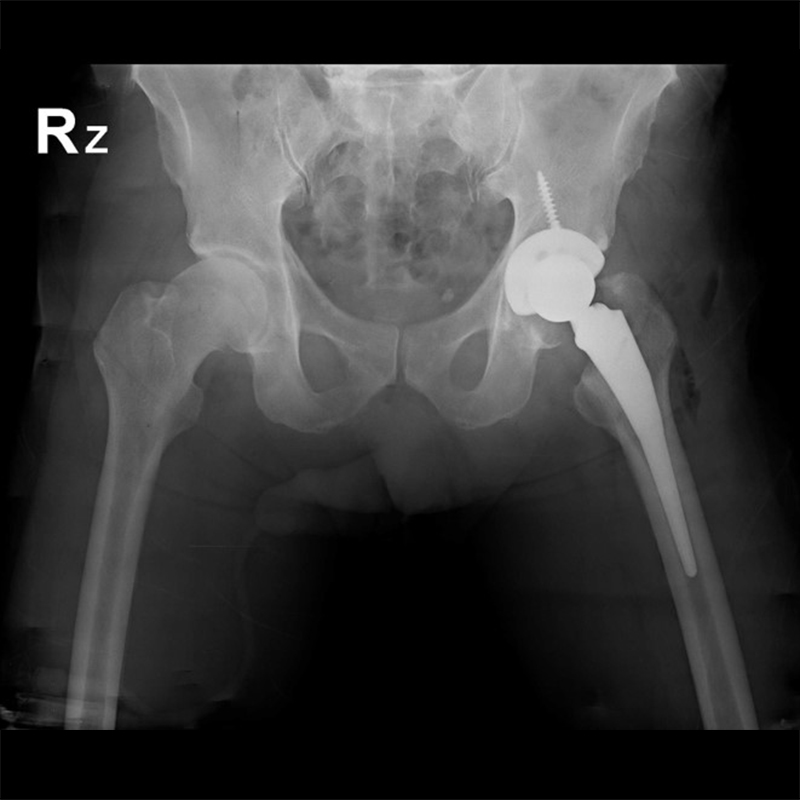

傳統髖關節置換 首頁 案例分享 髖關節手術 傳統髖關節置換 54歲蔡先生退化性關節炎 術前 術後 張女士 51歲 退化性關節炎(DDH先天發育不全 CROWE TYPE 2) 術前 術後 38歲林先生 退化性關節炎 術前 術後 72歲謝女士 退化性關節炎 術前 術後 71歲 謬女士 骨股頭壞死 術前 術後 50歲 郭先生骨股頭壞死 術前 術後 80歲 盧先生骨股頭壞死 術前 術後 林先生 37歲 術前 術後 邱女士 51歲 術前 術後 張女士 50歲 術前 術後